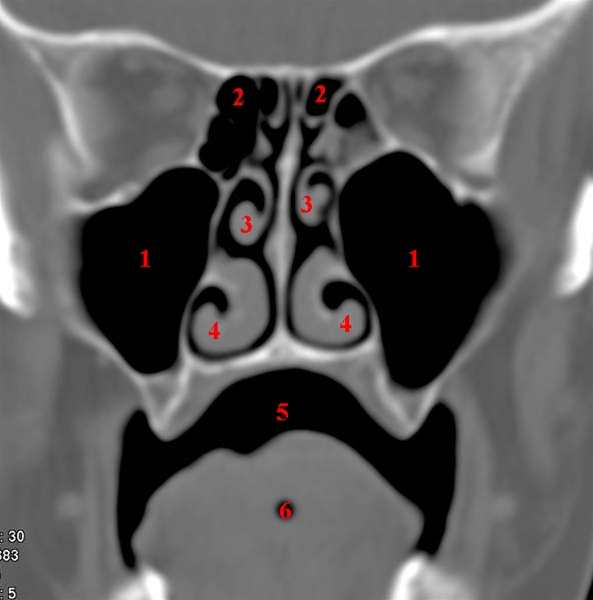

CT-snit i coronalplan gennem maxillarsinus.

1. Kæbehule (sinus maxillaris)

2. Sibenceller (sinus ethmoidales)

3. Mellemste næsemusling (concha nasalis media)

4. Nedre næsemusling (concha nasalis inferior)

5. Mundhule (cavum oris)

6. Tunge (lingua)